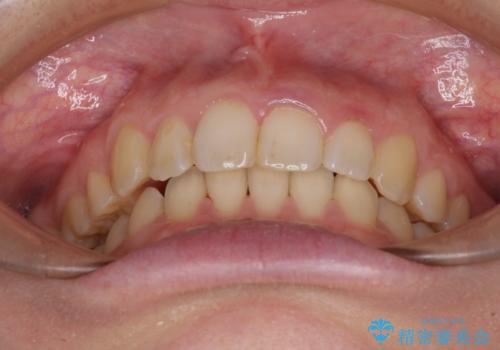

- 八重歯を気にして来院された患者様です。

八重歯の後ろの歯を1歯抜歯し、補助装置(リンガルアーチ)を用いて八重歯の位置を改善し、その後インビザラインにより矯正治療を行うこととしました。

下顎前歯が1本欠損したスリーインサイザーという状態であるため、上下の前歯の咬み込みが深くなったり、奥歯の咬み合わせが理想的なものとならなかったりという仕上がりになってしまいます。

前歯の見た目や奥歯の咬み合わせに、患者様が違和感を感じない状態として治療を終えました。